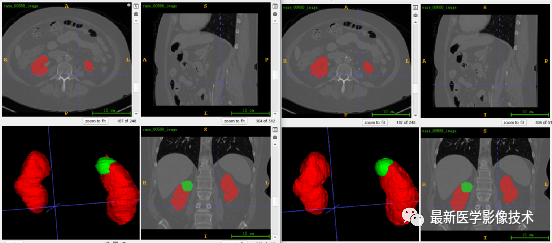

6、测试集分割结果、

左图是金标准结果,右图是预测结果。